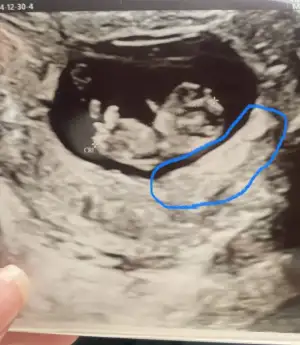

bakın burda çocuğum işemiş gibi görünüyor ama o aslında yolksacmış. Kesenin sağ alt kısmında bulunan kalın bi alan var ya orası için de plesanta dedi. Oluşmaya başlamış bir kaç haftaya görevi devralacak dedi. Ama doktor demese ben onun Plesenta oldğunu bilmezdim mesela

Tamm isteee o kesenin içindeki bebeği besleyen teşkilat eşi yani, kesenin iç kısmı, kese dediğimiz şey o yerleşim alanının adı

Kese ayrı plasenta ayrı o yüzden kesenin içinde doğuyor plasenta ise beslendiği yerBurası nasıl olabilir ki bebek nasıl içinde doğuyor o zaman bu işte bı terslik var bakicam şimdi![]()

O siyah alana kese diyoruz ya bebeklerin onun içinde plesantayla çevrili olduğunu ordan beslendiğini kazimisim beynime daha önce de gerekli olarak gördüğüm bilgi değilmiş demek ki şu ana kadar bakmamıştım guncellendim su an sayende teşekkürlerKuzucum valla ben de sağlıkçıyım ama laborantım o yüzden bu konularda çok da bilgim yok. Yani ben de yanılıyor olabilirim ancak internetten baktığım görsellerde de plesenta kenarda görünüyor bebeğin beslenmesine yardımcı. Bebeğin içinde bulunduğu o siyah şey kese bildiğim kadarıyla. Ama tabi bende yanılıyor olabilirim